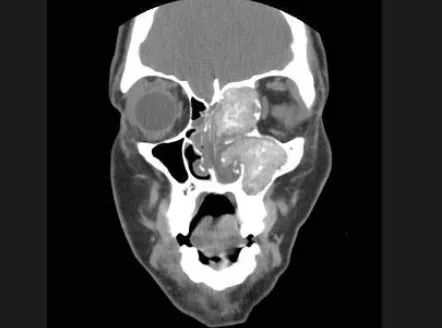

“麻烦你给看看孩子的脸和鼻子”。妈妈推着女儿进了门,摘掉了口罩和帽子。鼻腔养护师一看,皱起了眉头,左边单侧眉骨、颧骨比右边脸明显肿了很多,左边鼻翼宽大,因为左边面部浮肿,左边鼻孔比右边鼻孔高,肉眼非常明显就可观察到。鼻腔镜检查,鼻甲粘连,左侧中鼻道下鼻道完全堵塞。静静妈妈带来了CT片,和诊断书。

鼻腔养护师问:这种情况多久了?母亲想了想,从确诊为鼻窦炎到现在已经有半年了,脸浮肿也就高考几天。以前也没这么严重,这几天老说头痛鼻塞,我也没在意,我以为孩子偷懒不想复习,给喷了点药,没想到几天后脸就肿起来了。没想到孩子高考那几天,更严重了。孩子答完卷根本没检查就出考场了,本来孩子能考上北大……